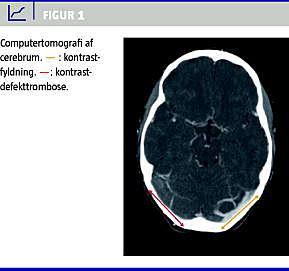

Ved en CT uden kontrast af cerebrum fandt man hyperdense strøg i højre sinus sigmoideus og transversus. På mistanke om sinustrombose blev der foretaget en CT-angiografi, som viste en kontrastdefekt i sinus transversus, sinus sigmoideus og vena jugularis på højre side, hvilket er foreneligt med sinusvenetrombose (Figur 1 ).